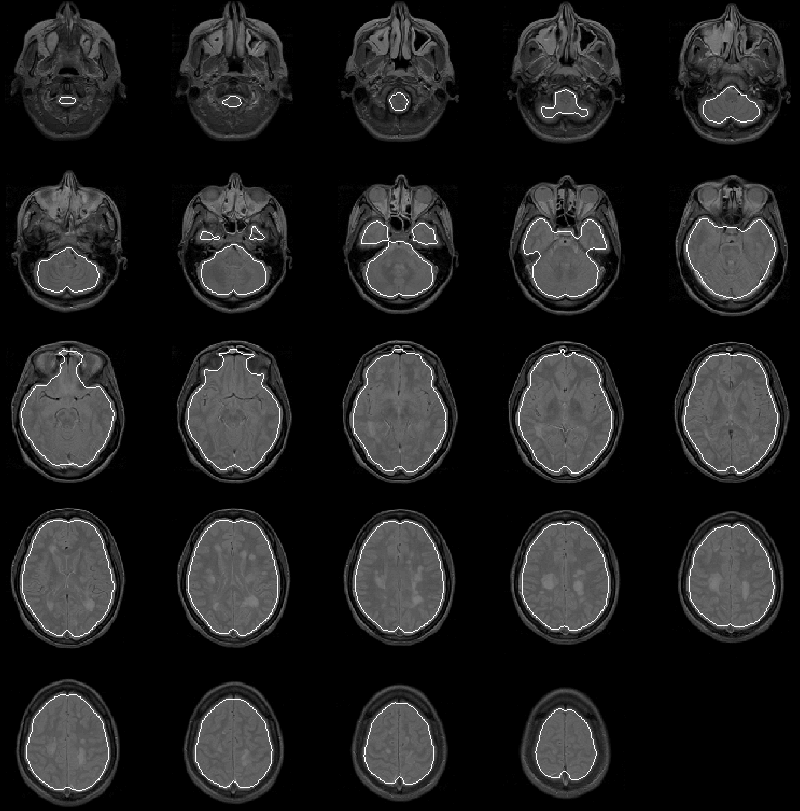

The initial brain mask for Data Set 1, produced by the Generate Initial Brain Mask process, is overlaid on the PD-weighted MR volume in Figure 8.11. Slice 7 is enlarged in Figure 8.12.

Figure 8.11: The initial brain mask for MRI Data Set 1 overlaid on the PD-weighted scan.

The mask apparently identifies all brain tissue regions. Its boundary falls consistently close to, and inside, the intracranial boundary. The initial brain mask should be an ideal seed for the Generate Final Brain Mask process which uses the active contour model algorithm with balloon forces to push the mask boundary outward.